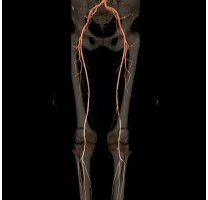

L’Angio-scanner

Cet examen est très utilisé et donne d’excellents renseignements sur l’arbre artériel depuis l’aorte jusqu’au tiers proximaux des artères de jambes. Il nécessite l’injection d’iode. Il permet une étude de la paroi artérielle et visualise les calcifications, ces calcifications peuvent parfois gêner l’interprétation.

ANGIO-SCANNER